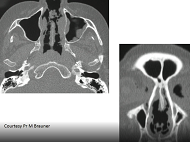

Quel bilan préconiser au diagnostic et pour le suivi dune sarcoïdose pulmonaire ?

- Date : 25/01/2019

- 0

0